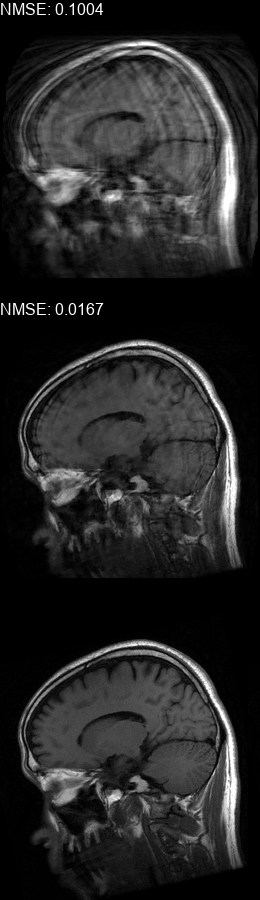

Results  Experimental results using the two presented datasets, for the fully-sampled and under-sampled k𝑘k-space scan orders, are shown in Table 1. The table presents the Normalized Mean Square Error (NMSE) obtained for each of the scan orders. For the Transaxial dataset, we only show the results for the challenging task where the DP contains only up to 707070 columns of k𝑘k-space data. All methods are able to reduce the NMSE of the corrupted scans, however the methods that incorporate the DC layer achieve a much better result. These results match our subjective visual impression of the motion-corrected images, as may be seen in Fig. 3 for simulated motion in a fully-sampled k𝑘k-space data, and Fig. 4 for an under-sampled k𝑘k-space data.

Figure 3: Motion corrected images from the Diverse dataset calculated using the 𝒮260subscript𝒮260\mathcal{FS}_{260} scan order presented in Fig. 1b. The bottom row shows the motion-free image. The top row shows the motion-corrupted images. The middle row shows the corrected images calculated using our method. (a) contains a motion at t1=87subscript𝑡187t_{1}=87, (b) contains two motions at t1=46subscript𝑡146t_{1}\!=\!46, t2=170subscript𝑡2170t_{2}\!=\!170, (c) contains three motions at t1=72subscript𝑡172t_{1}\!=\!72, t2=227subscript𝑡2227t_{2}\!=\!227, t3=248subscript𝑡3248t_{3}\!=\!248, (d) contains two motions at t1=112subscript𝑡1112t_{1}\!=\!112, t2=216subscript𝑡2216t_{2}\!=\!216, (e) contains a motion at t1=66subscript𝑡166t_{1}\!=\!66, (f) contains three motions at t1=65subscript𝑡165t_{1}=65, t2=135subscript𝑡2135t_{2}\!=\!135, t3=159subscript𝑡3159t_{3}\!=\!159.